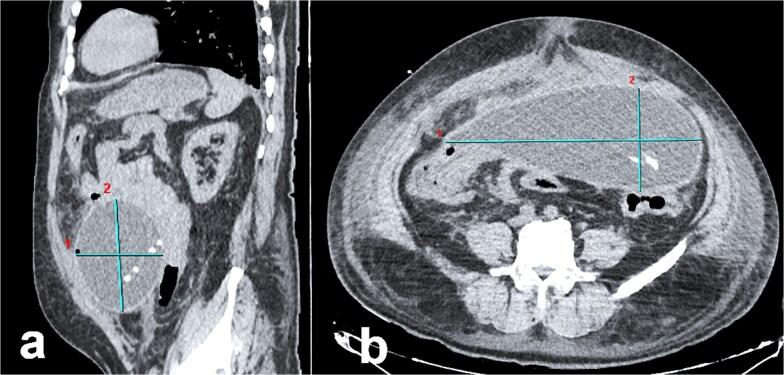

Peritoneal pseudocysts are benign, fluid-filled structures that arise from the accumulation of intra-abdominal fluid, which would typically be reabsorbed by the peritoneum. These pseudocysts form when peritoneal integrity is disrupted by adhesions, often secondary to trauma, surgery, or infection. While intraperitoneal pseudocysts are rare, they are most frequently associated with inflammatory processes, including ventriculoperitoneal shunt complications, catheter-related infections. Sclerosing peritonitis (SP), a rare but serious complication of long-term continuous ambulatory peritoneal dialysis, is characterized by marked thickening of the peritoneal membranes. Histologically, these membranes consist of dense fibrotic connective tissue infiltrated by mononuclear and polymorphonuclear cells. The pathogenesis of SP-associated pseudocysts is thought to involve low-grade infection or localized chronic inflammation. A 59-year-old male on peritoneal dialysis presented to the emergency department with chronic abdominal pain. Computed tomography imaging revealed a large peritoneal pseudocyst. During exploratory midline laparotomy, the pseudocyst was successfully evacuated, and the peritoneal dialysis catheter was removed.

腹膜假性囊肿是良性的、充满液体的结构,由腹腔内液体积聚形成,这些液体通常会被腹膜重新吸收。当腹膜完整性因粘连而破坏时会形成这些假性囊肿,粘连常继发于创伤、手术或感染。虽然腹腔内假性囊肿罕见,但它们最常与炎症过程相关,包括脑室腹腔分流并发症、导管相关感染。硬化性腹膜炎(SP)是长期持续性非卧床腹膜透析的一种罕见但严重的并发症,其特征是腹膜显著增厚。从组织学上看,这些腹膜由被单核细胞和多形核细胞浸润的致密纤维结缔组织组成。SP相关假性囊肿的发病机制被认为与低度感染或局部慢性炎症有关。一名接受腹膜透析的59岁男性因慢性腹痛就诊于急诊科。计算机断层扫描成像显示一个大的腹膜假性囊肿。在中线剖腹探查术中,假性囊肿被成功排空,腹膜透析导管被移除。